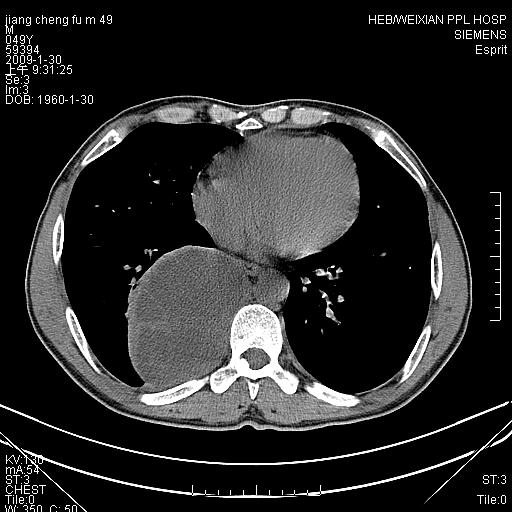

男性,49岁,主因胸痛,右肺呼吸音低。胸片提示肺占位

考虑右侧脊柱旁沟囊性病变。1:支气管囊肿或食管囊;2:神经源性肿瘤。

右后纵隔囊性占位;考虑为:1)淋巴管囊肿。2)食管囊肿。建议:进一步检查。

右后纵隔囊性占位,建议先做增强,后做穿刺活检。

在分析这个病变时,首先病灶边界清晰,但其内密度不均匀,有条索状状实性成分,肿块的外侧壁亦呈一不均匀的厚壁改变,因此支气管囊肿的可能性不大。主要考虑神经源性肿瘤(主要考虑神经鞘瘤,因为它囊变的机率比较高),其次考虑肺膈离征,行增强扫描如发现来自胸主动脉供血动脉血管可确诊。

考虑右侧脊柱旁沟囊性病变,囊骨有分隔,囊壁较厚。1:神经源性肿瘤;2:食管囊肿或淋巴管囊肿。支持!

囊状肿块内有线样软组织分隔,支气管囊肿及食管囊肿可不考虑。我考虑:1、囊性肺膈离征(需要增强扫描来排除)。2、神经鞘瘤。3、淋巴管囊肿。